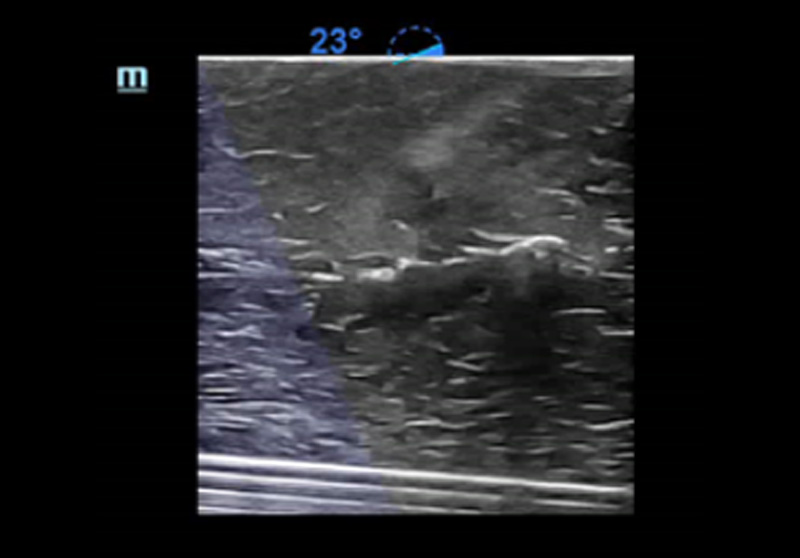

1Smart B-line

Tel automatisch het aantal B-lijnen en het percentage van de oppervlakte van B-lijnen volgens de protocollen. En scoor de prestaties van de long in vier patronen volgens de longbeluchting. Beeldoverzicht en kleurenkaart van de score kunnen helpen bij de beoordeling van de longfunctie.